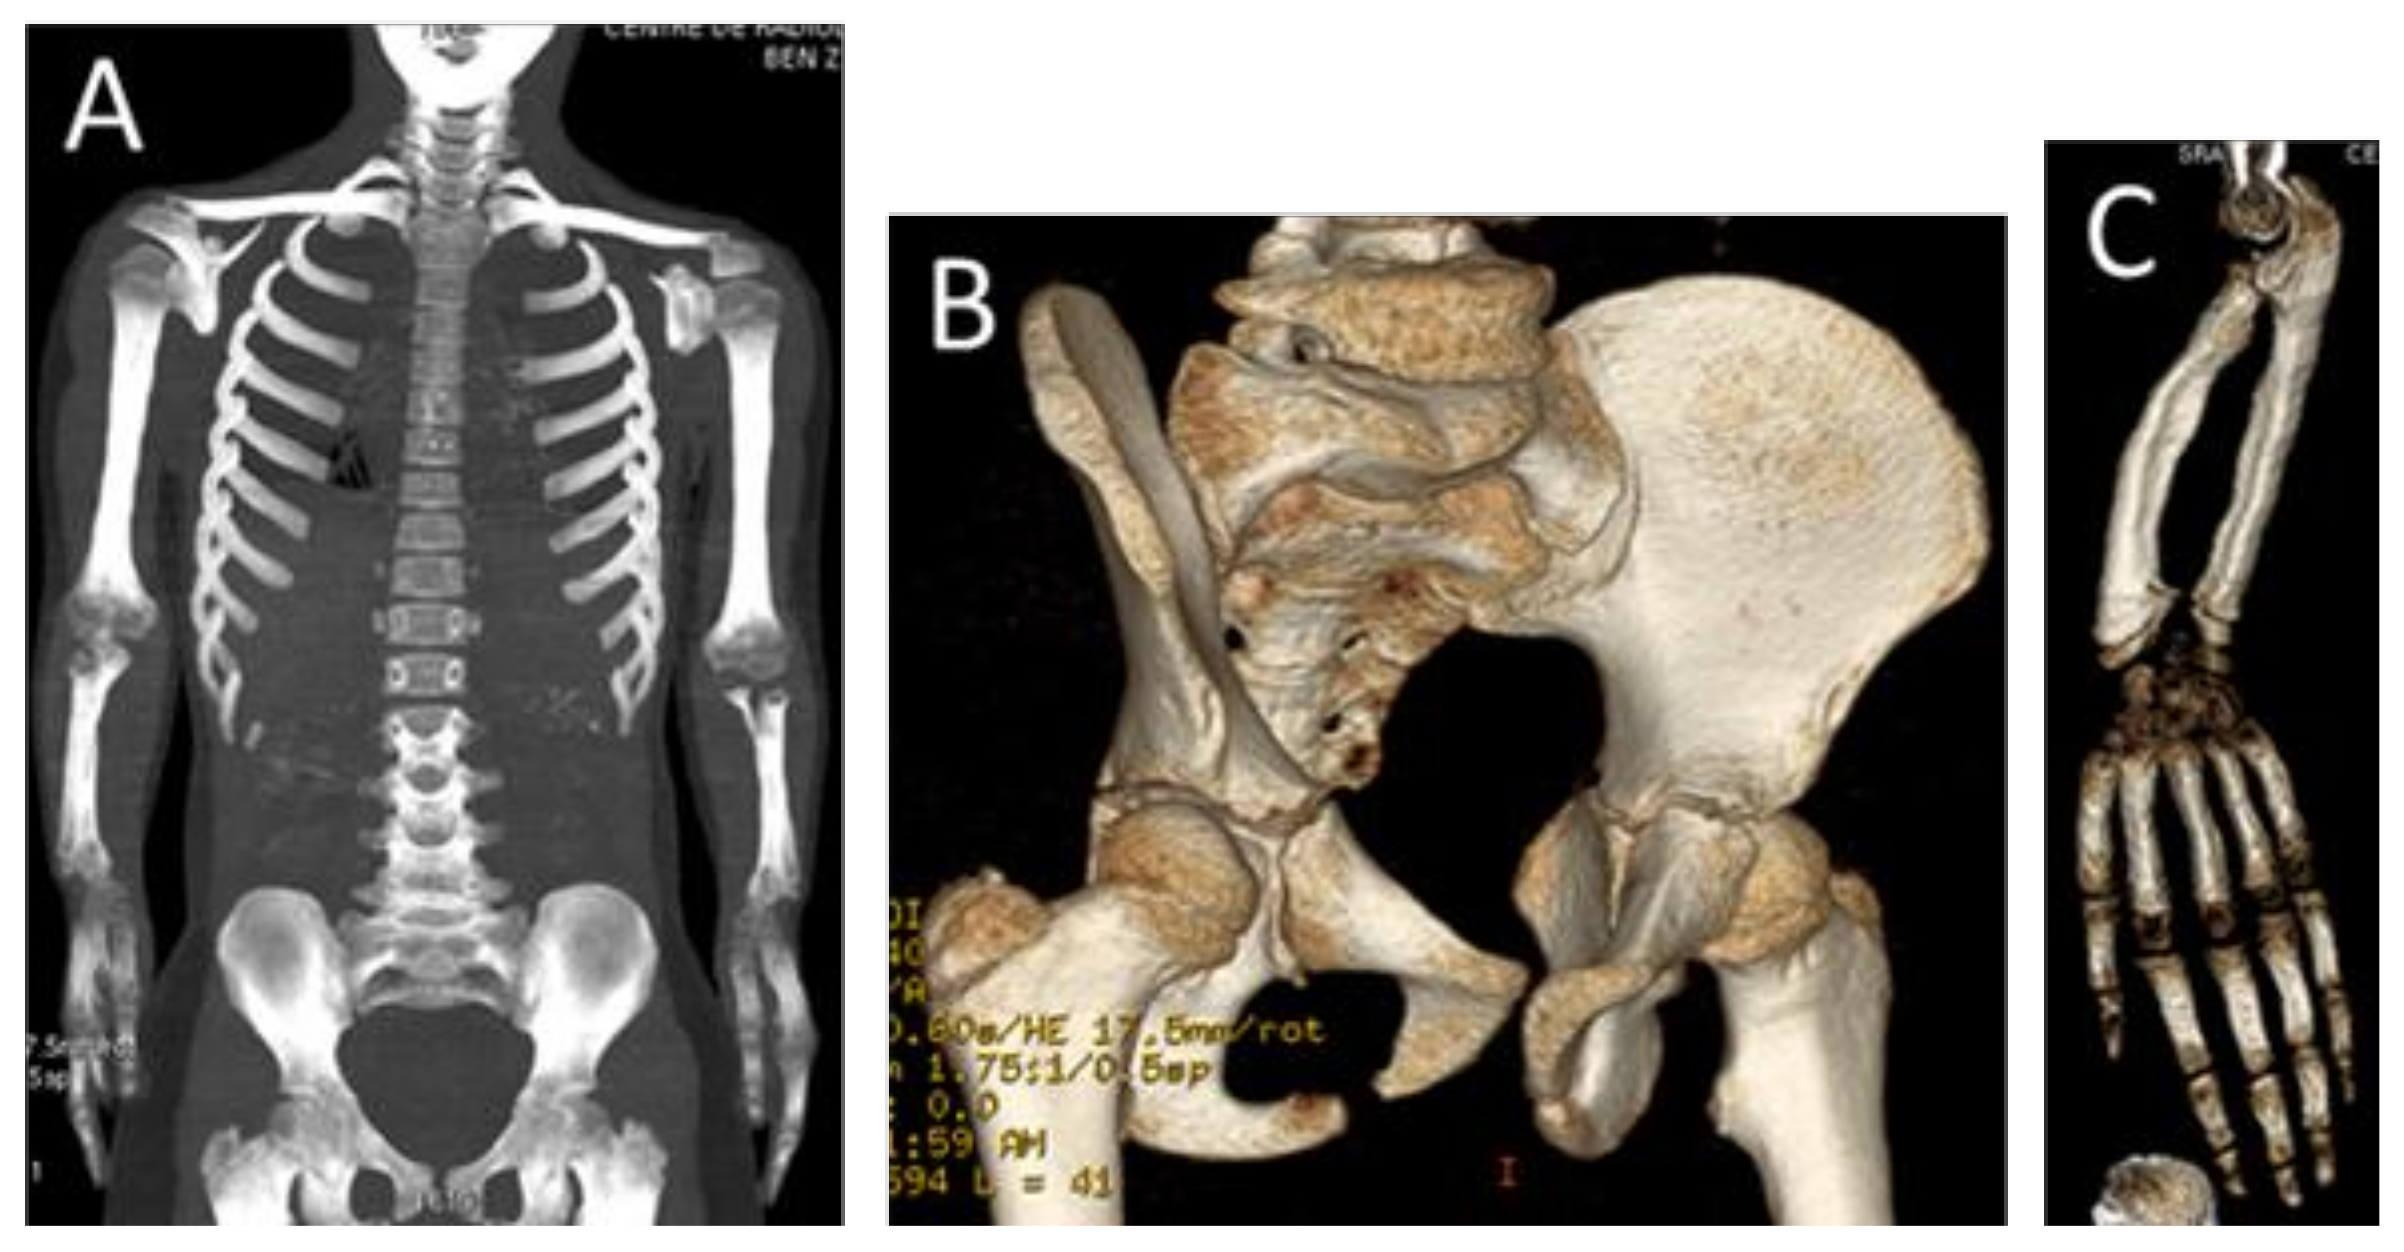

Leri-Weill Dyschondrosteosis Syndrome: Analysis via 3DCT Scan